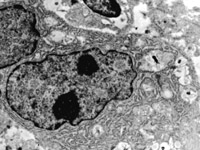

5-2-2 伤后第1天,毛细血管内皮细胞核固缩,管腔内血液凝聚和瘀滞  TEM×6000